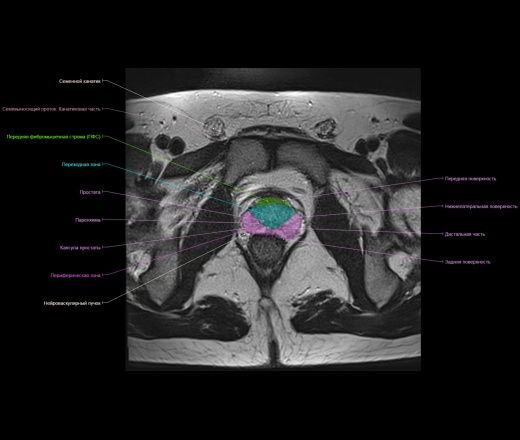

Представленный материал носит обучающий характер, не стал размещать в разделе Презентации, из за отсутствия вьюера с возможностью именно прокручивать изображения как на рабочей станции.

https://www.imaios.com/ru/e-Anatomy/Grudnaya-kletka-bryushnaya-polost-taz/Muzhskoj-taz-MRT

https://radiopaedia.org/cases/normal-prostate-mri

http://event.medradiology.moscow/d/1387577/d/mrt_predstatelnoy_zhelezy.pdf

Надписи очень плохо видно, разместил в разделе Презентации там видно получше.